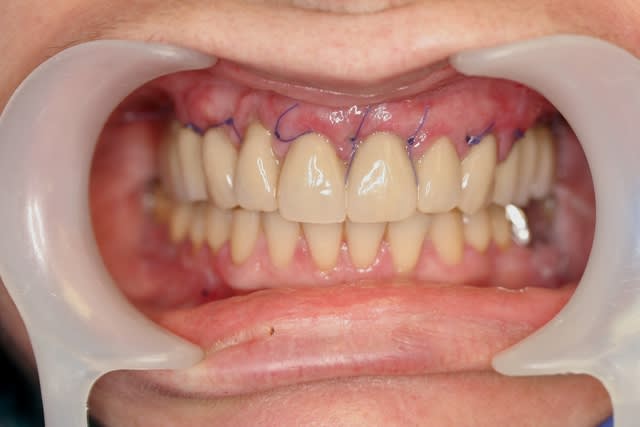

l'autre aspect de l'intervention, qui a aussi conditionné ce choix de 1 implant/dent, c'est que je voulais au niveau esthétique être le plus proche du naturel et que le provisoire soit en fait une prothèse de longue durée, esthétique et fonctionnelle

impossible à faire réellement avec du transvissé en MCI, même avec Posit alors que là...

mention spéciale pour Posit...sa maîtrise dans le montage cosmétique (résine pourtant!!!) est proche des céramiques

sympa l'aspect gingival sur la dernière photo de la prothèse en place avec les écarteurs